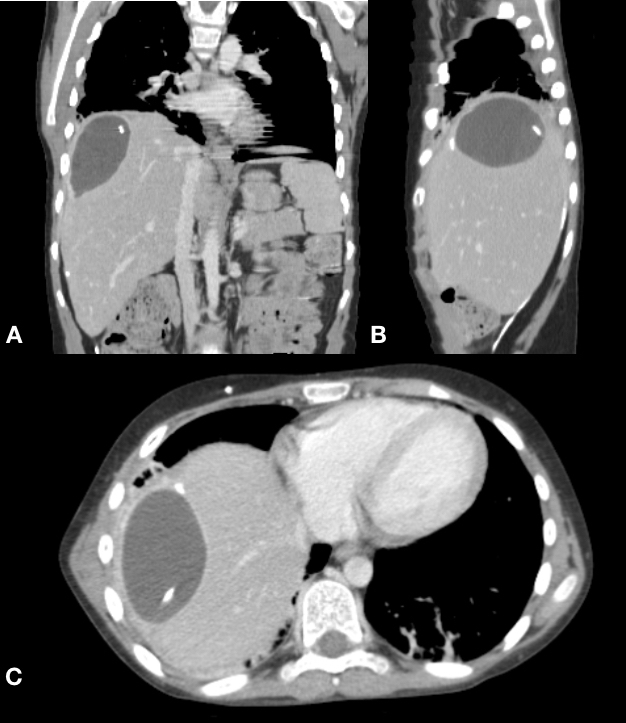

The clinical image is a computed tomography (CT) scan of the abdomen in the coronal (A), sagittal (B) and axial (C) incidences. We observe an intrahepatic (segment VII) CSF containing cyst along with the VP shunt distal tip. A 12-year-old male patient underwent a VP shunt due to hydrocephalus from tumoral etiology (craniopharyngioma). The patient had already had the shunt for 7 months when he started with severe abdominal pain on the right flank. An abdominal CT scan disclosed this rare finding. He underwent surgery to revise the shunt with repositioned towards inferior left quadrant of the abdomen. CSF analysis showed that there were no signs of infection. The patient did well without further complications. We reviewed the medical literature worldwide and found only 13 reports of intrahepatic CSF pseudocysts [1-5].